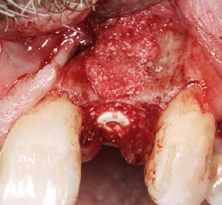

Der klinische Befund zeigte eine definitive Versorgung auf 12 und eine temporäre Versorgung auf 22. Dahingegen lag bei der Implantatversorgung in regio 22 der Verdacht auf eine partielle Fibro-Osseointegration vor (Abb. 1 und 2) [9,10].

Der chirurgische Eingriff wurde unter Lokalanästhesie mit palatinaler und labialer Infiltration durchgeführt. Zuerst erfolgte die Entfernung des Implantats. Für die Explantation wählten wir das aus unserer Sicht knochenschonendste Verfahren. Mithilfe einer Extraktionszange und mit entsprechend dosierter Kraft drehten wir das teilweise ankylotische Implantat in Achsrichtung aus, um auf jeden Fall die dünne labiale Knochenlamelle zu erhalten (Abb. 3). Dabei frakturierte der osseointegrierte Implantatapex tief im Implantatbett (Abb. 4). Um diesen zu entfernen, musste ein minimalinvasiver apikaler Zugang geschaffen werden. Nach einer krestalen Inzision mit mesialer Tunnelpräparation und distaler Entlastungsinzision sowie der Präparation eines Mukoperiostlappens zeigte sich ein ausgeprägter konkaver Alveolarknochen. Mit einem piezotechnisch unterstützten Chirurgieansatz fenestrierten wir die labiale Knochenlamelle (Abb. 5). Durch diesen minimalinvasiven Zugang lösten wir die ankylotische Verbindung und entfernten den apikalen Implantatrest. Bei dieser Methode der Implantatentfernung wird der periimplantäre krestale Knochen weitestgehend geschont.